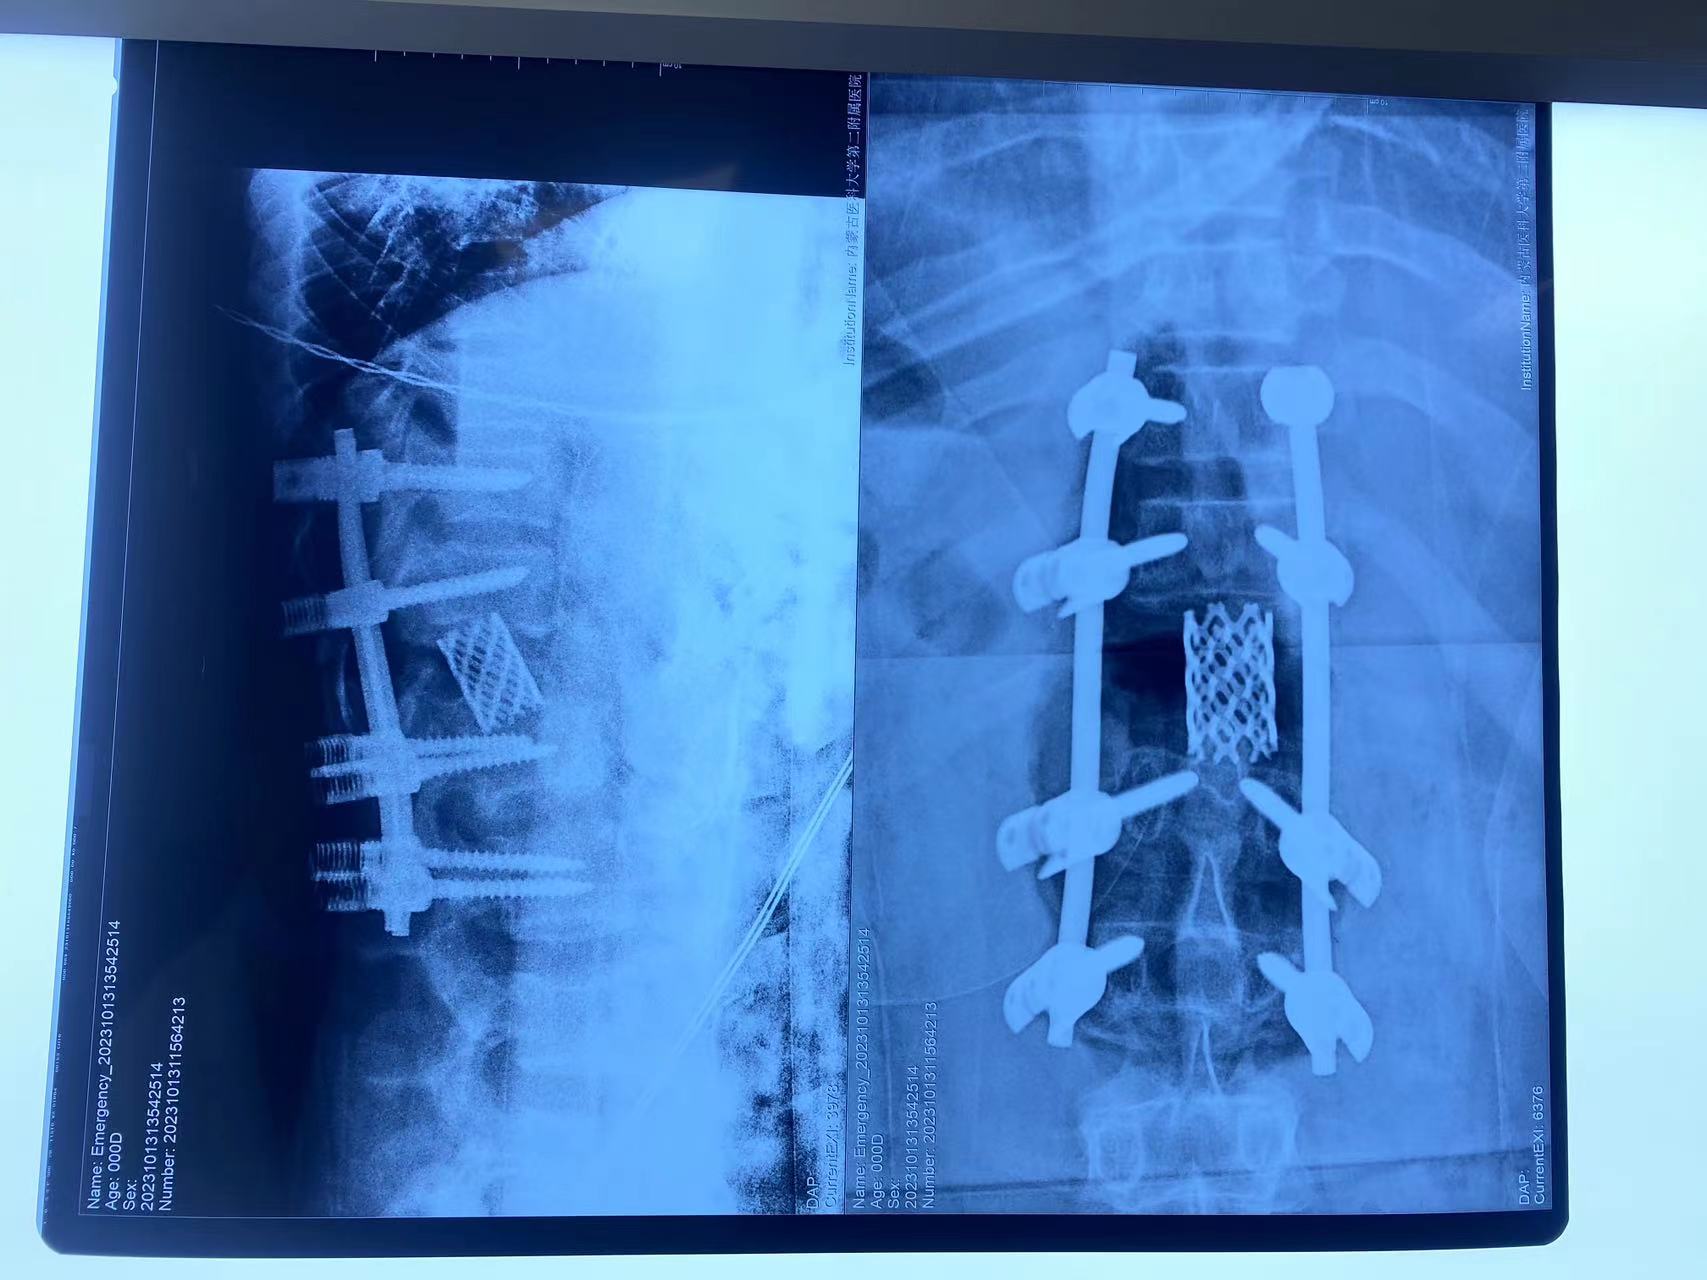

脊柱外科中心D区辛大奇、王东海、孙洪岩医疗团队完善患者术前检查后,明确诊断为胸12半椎体侧后凸畸形,经过积极与胡侦明教授沟通、讨论后,共同为患者制定手术方案,为患者施行先天性脊柱侧弯、半椎体侧后凸畸形截骨矫形+植骨融合内固定术。

胡侦明教授不远万里,亲临91直播 参加会诊并给予手术指导,最终在胡教授和91直播 医护团队的通力协作下,手术顺利完成,患者术后继续接受恢复治疗,状态良好,患者双下肢功能明显改善。近日,患者已顺利康复出院。